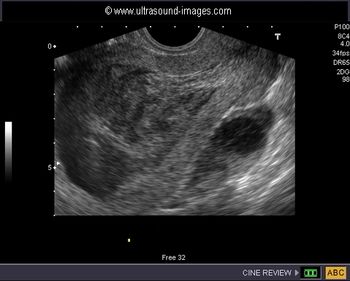

Excessive traction blamed for brachial plexus injury; bowel injury after laparoscopy; prolonged second stage blamed for CP; failure to perform timely cesarean blamed for child’s developmental delay; uterus perforated during hysteroscopy; severe IUGR not detected in high-risk pregnancy